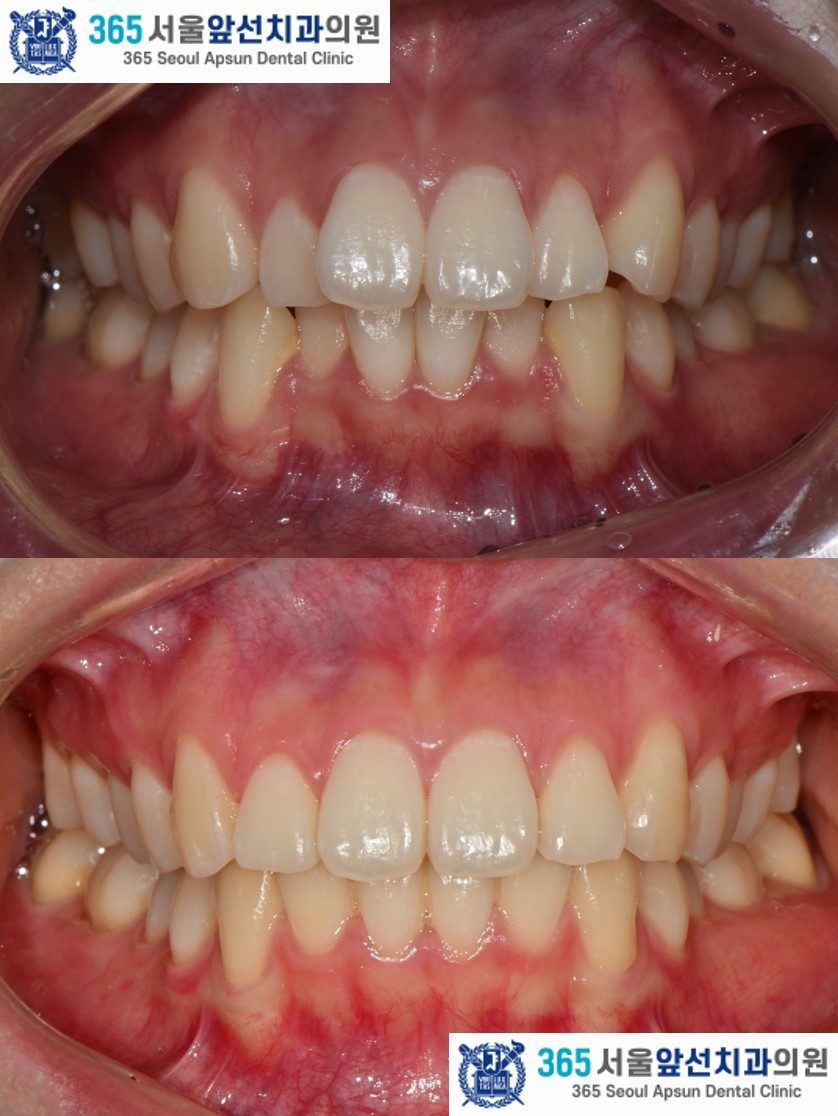

치료 후의 모습입니다. 아랫니 치열은 약 5개월, 윗니 치열은 약 7개월의 치료기간이 소요되었습니다. 앞니의 치열이 가지런하게 배열되어 환자분도 만족하셨습니다. 미소 시 자연스럽고 단정한 인상으로 변화하였습니다. 앞니 부분 교정 증례의 치료기간은 4-9개월 사이로 정도에 따라 상이합니다. 부분 교정 관심 있으신 환자분들께서는 365서울앞선치과로 내원하셔서 교정 진단 받아보시길 바랍니다. 감사합니다!

gif 촬영일자 2025.02.25. 2025.03.26. 2025.04.26. 2025.05.28. 2025.11.06. 2025.02.25. 2025.11.06. 2025.02.25. 2025.11.06. 2025.02.25. 2025.11.06. |